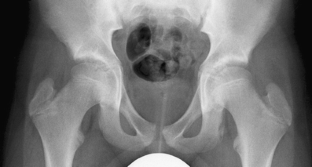

Fig. 2